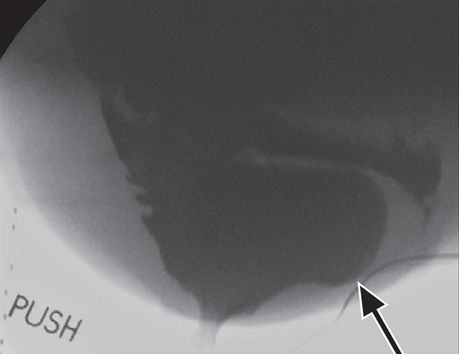

典型的直肠前突是指直肠向前方膨大,引起直肠阴道隔和阴道后壁的异常膨隆。肛管向前膨大范围在2cm以内是生理性的。较大的直肠前突经常和排空不完全有关(图3)。肛门提肌复合体的松弛或缺损,有时和直肠侧方突出至坐骨直肠窝有关,MRI是诊断的最佳方法。

图3 传统排便造影图显示的直肠膨出。可见力排期—较大的向前方膨隆的结构(箭)。注意阴道也有钡剂,由于直肠膨出的影响,阴道和直肠阴道隔走行几乎为水平方向